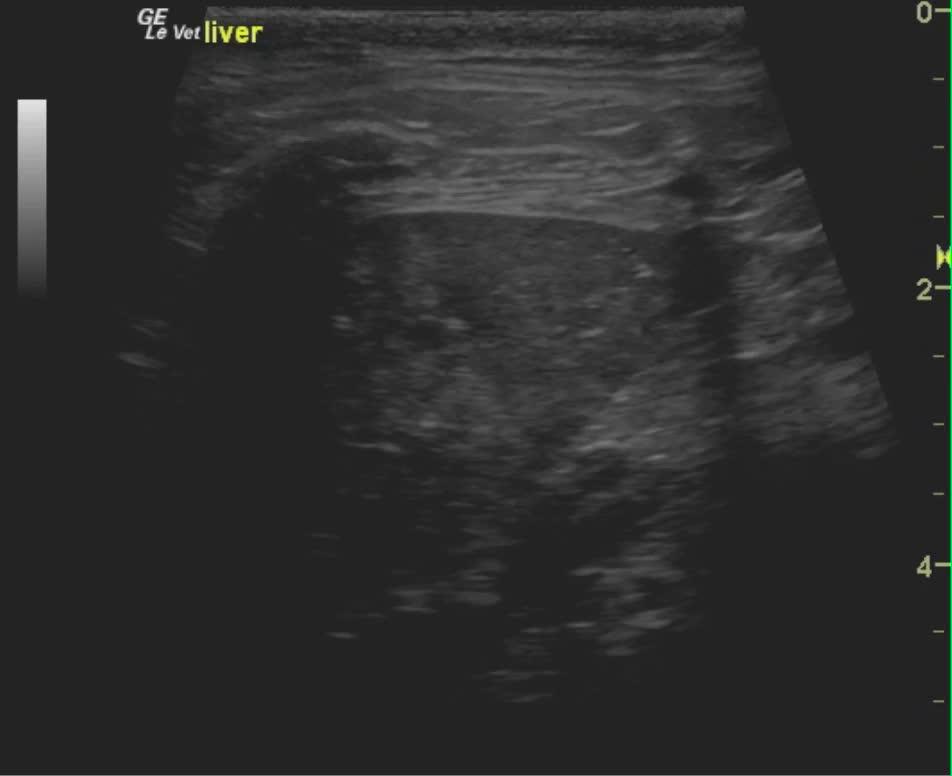

A 9-year-old MN DSH was presented for evaluation of lethargy, inappetence, and diarrhea. On physical examination, moderate dental tartar, poor body condition (BCS 2/5) and a dull unkempt hair coat was evident. On urinalysis moderate leukosuria, mild hematuria, and normal SG with moderate leukocytes, 2+ protein, 6.5 pH, urine specific gravity 1.035 with a small amount of blood. Abnormalities on CBC and serum biochemistry were neutrophilia with toxic changes, hyperglycemia, hyperglobulinemia, elevated fPL, and low folate and low B12. Negative FeLV, negative FIV, and negative heartworm assay. On survey radiographs mild hepatomegaly was evident.